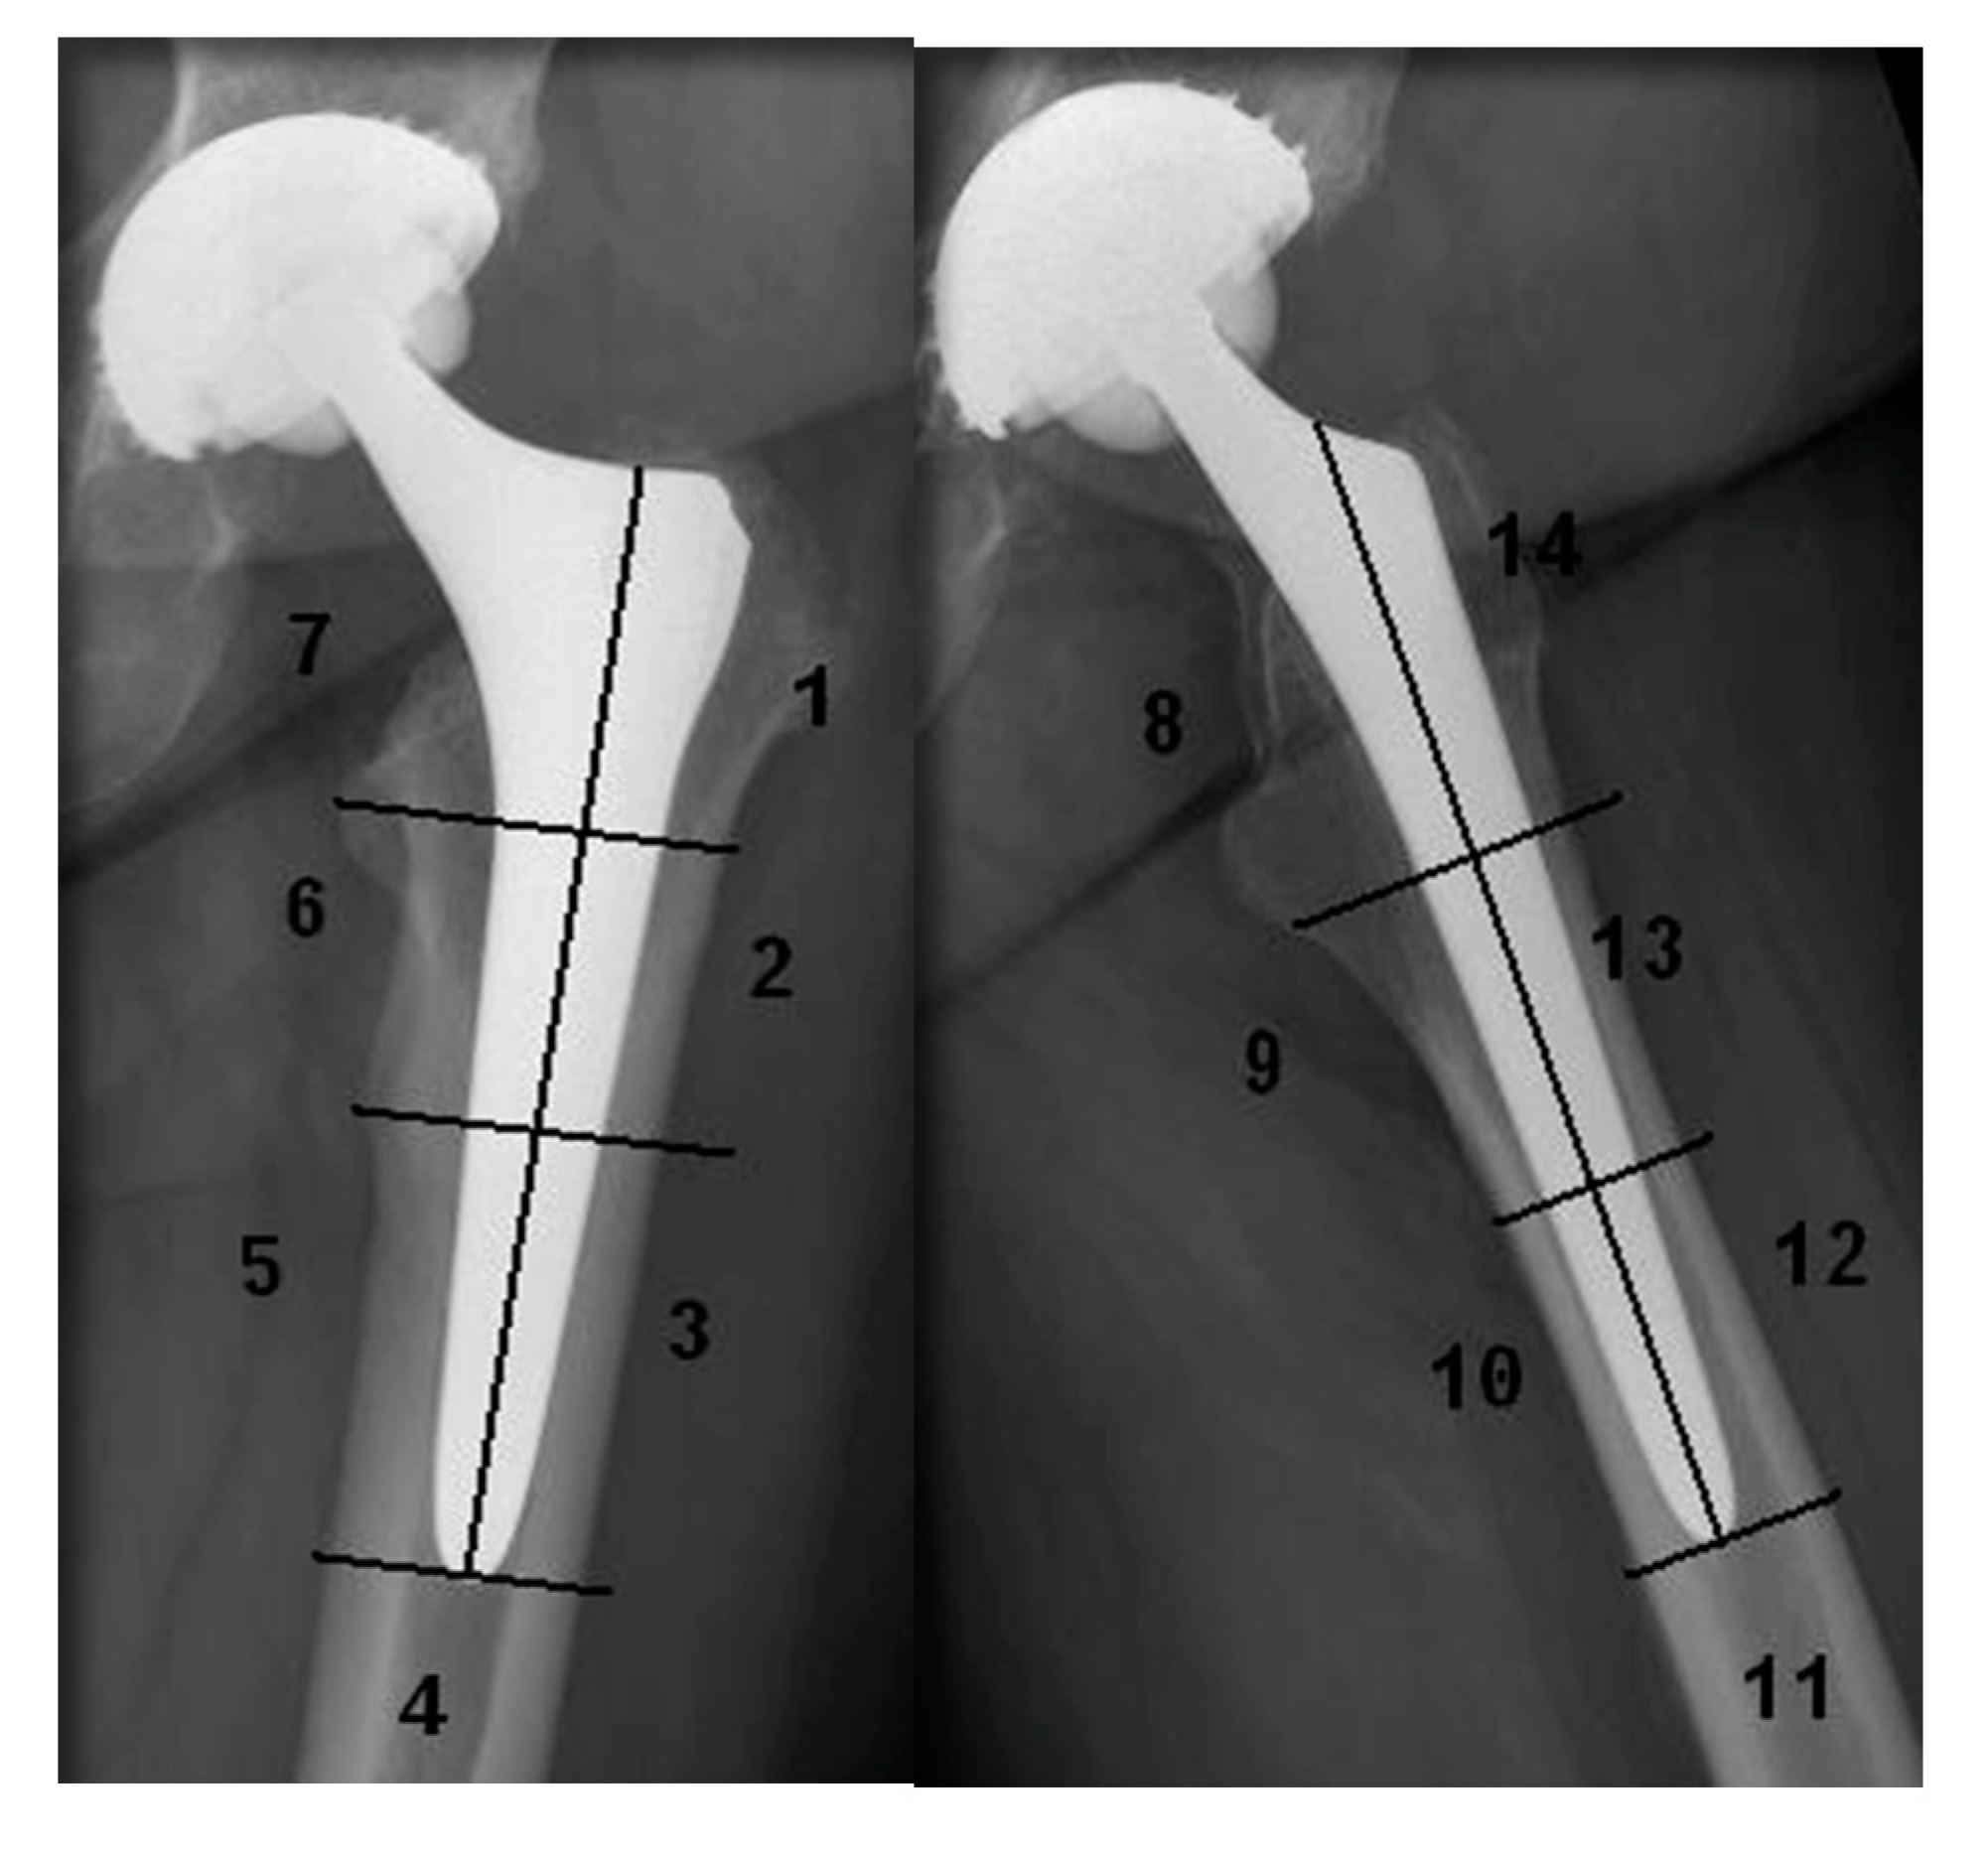

| Radiolucent Lines-Stem [17] | ||||

|---|---|---|---|---|

| Cases with Radiolucent Lines | <1 mm | 1–3 mm | >3 mm | |

| S1 | 64.04% | 56.14% | 35.08% | 8.77% |

| S2 | 20.22% | 61.11% | 27.77% | 11.11% |

| S3 | 2.25% | 0% | 100% | 0% |

| S4 | 1.12% | 100% | 0% | 0% |

| S5 | 3.37% | 100% | 0% | 0% |

| S6 | 20.22% | 66.66% | 33.33% | 0% |

| S7 | 46.06% | 39.02% | 51.21% | 9.76% |

| S8 | 58.13% | 52% | 40% | 8% |

| S9 | 26.74% | 39.13% | 43.47% | 17.39% |

| S10 | 1.16% | 100% | 0% | 0% |

| S11 | 1.16% | 100% | 0% | 0% |

| S12 | 1.16% | 0% | 100% | 0% |

| S13 | 17.44% | 46.66% | 26.66% | 26.66% |

| S14 | 58.13% | 52% | 42% | 16% |